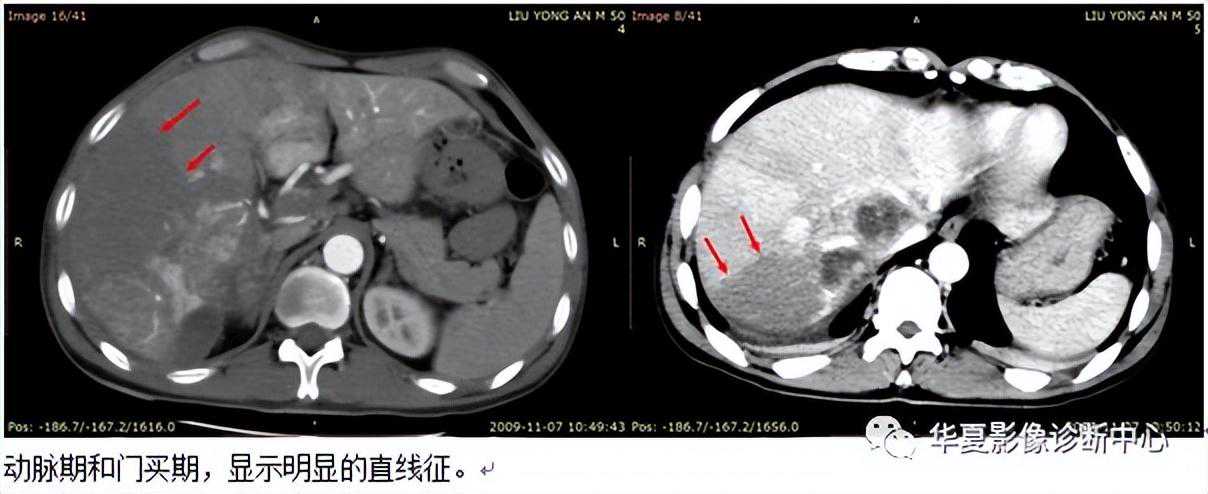

019:直线征

【影像表现】经动脉门脉造影CT(CTAP)肝实质内出现三角形或楔形低密度区,其与增强肝实质之间出现的直线样分界线,此线从肿块延伸至肝脏边缘,称为直线征。

【征象解释】直线征是肝脏肿瘤直接侵犯或血凝块阻塞门静脉分支的CTAP表现,以肝癌多见。三角形或楔形低密度区代表受累门静脉分支远侧低灌注区,增强肝实质代表门静脉分支血流量正常灌注区。

【讨论】直线征由Tyrrel等在1989年首先描述并正式命名。

CTAP是近年来提出的一种CT与血管造影术相结合的新的影像学检查方法,是将造影剂经导管注人肠系膜上动脉或脾动脉、于门静脉期CT扫描所获图像。其基本原理是,正常肝脏为双重供血,肝动脉供应的血液占20%~75%,门静脉占75%~80%。但肝脏绝大多数肿瘤仅有肝动脉供血,少数还有门静脉供血。正常肝实质与肝肿瘤之间血流灌注的差异是CTAP检测肝脏肿瘤的主要生理及病理学从础。CTAP的成功实施是由于门静脉山肠系膜上静脉和脾静脉汇合而成,对比剂由肠系膜上动脉或脾动脉注入后,经部分肠道或脾循环回流入门静脉至肝脏,使正常肝组织达到最大限度的强化,而大部分肝肿瘤无门静脉供血表现为低密度灶,与明显强化的肝实质形成强烈对比而被检出。

直线征首先由Tyrrel等提出。是指肝脏中央的肿瘤,其远侧低灌注区表现为较大楔形或扇形灌注缺损。形态沿肝叶或肝段分布,从肝脏中心部分指向包膜,与增强肝实质之间出现的直线样分界线。直线征形成的原因为邻近肿瘤的门静脉被肿瘤组织直接侵犯、门静脉瘤栓或肝门处的肿瘤压迫门静脉分支而造成门静脉管腔阻塞所致。文献报道,肝癌CTAP检查该征出现率为11.5%、36%及38.5%不等,但其共同特点是呈现典型的楔形或扇形灌注缺损。缺损的近侧在延迟CTAP或MRI检查时均显示有一大小不等肿块影,邻近门静脉显示不清、阻断或变窄,直线征也都消失。该征出现常提示肝脏肿瘤邻近门静脉受累及其所供血范围肝组织血流障碍,一方面有助于评价肿瘤真正的大小及与周围的关系,另一方面有助于临床制定不同的治疗计划口当怀疑直线征存在时,延迟CTAP及MRI检查是必要的,因为多数病例在延迟:CTAP和(或)MRI检查时,显示出病变的位置,并显示出病变远侧的正常肝组织,DSA经动脉门静脉造影有助于进一步确定门睁脉阻塞的部位及形成阻塞的原因。

CTAP时,肝实质呈密度均匀的普遍强化,而肿瘤组织由于血供因素表现为低密度区。但灌注异常区并不意味着肿瘤,它可能是良性或恶性肿瘤,也可能是非肿瘤的灌注异常,即非肿瘤性灌注缺损(又称为假阳性病变),后者主要原因很多、主要包括肝纤维化、局灶性脂肪浸润、变性结节、肝静脉未强化、解剖变异、肝门静脉栓塞等。

总之,在CTPA上直线征主要是由肿瘤或血栓阻塞门静脉引起。对于中心性肝细胞癌,此征具有非常重要的意义,因为出现此征即意味着肿瘤不可切除;而对于转移瘤患者,出现此征员然井不表示不能行手术治疗甲但至少可以提示外科医师肿瘤与门静脉关系密切。